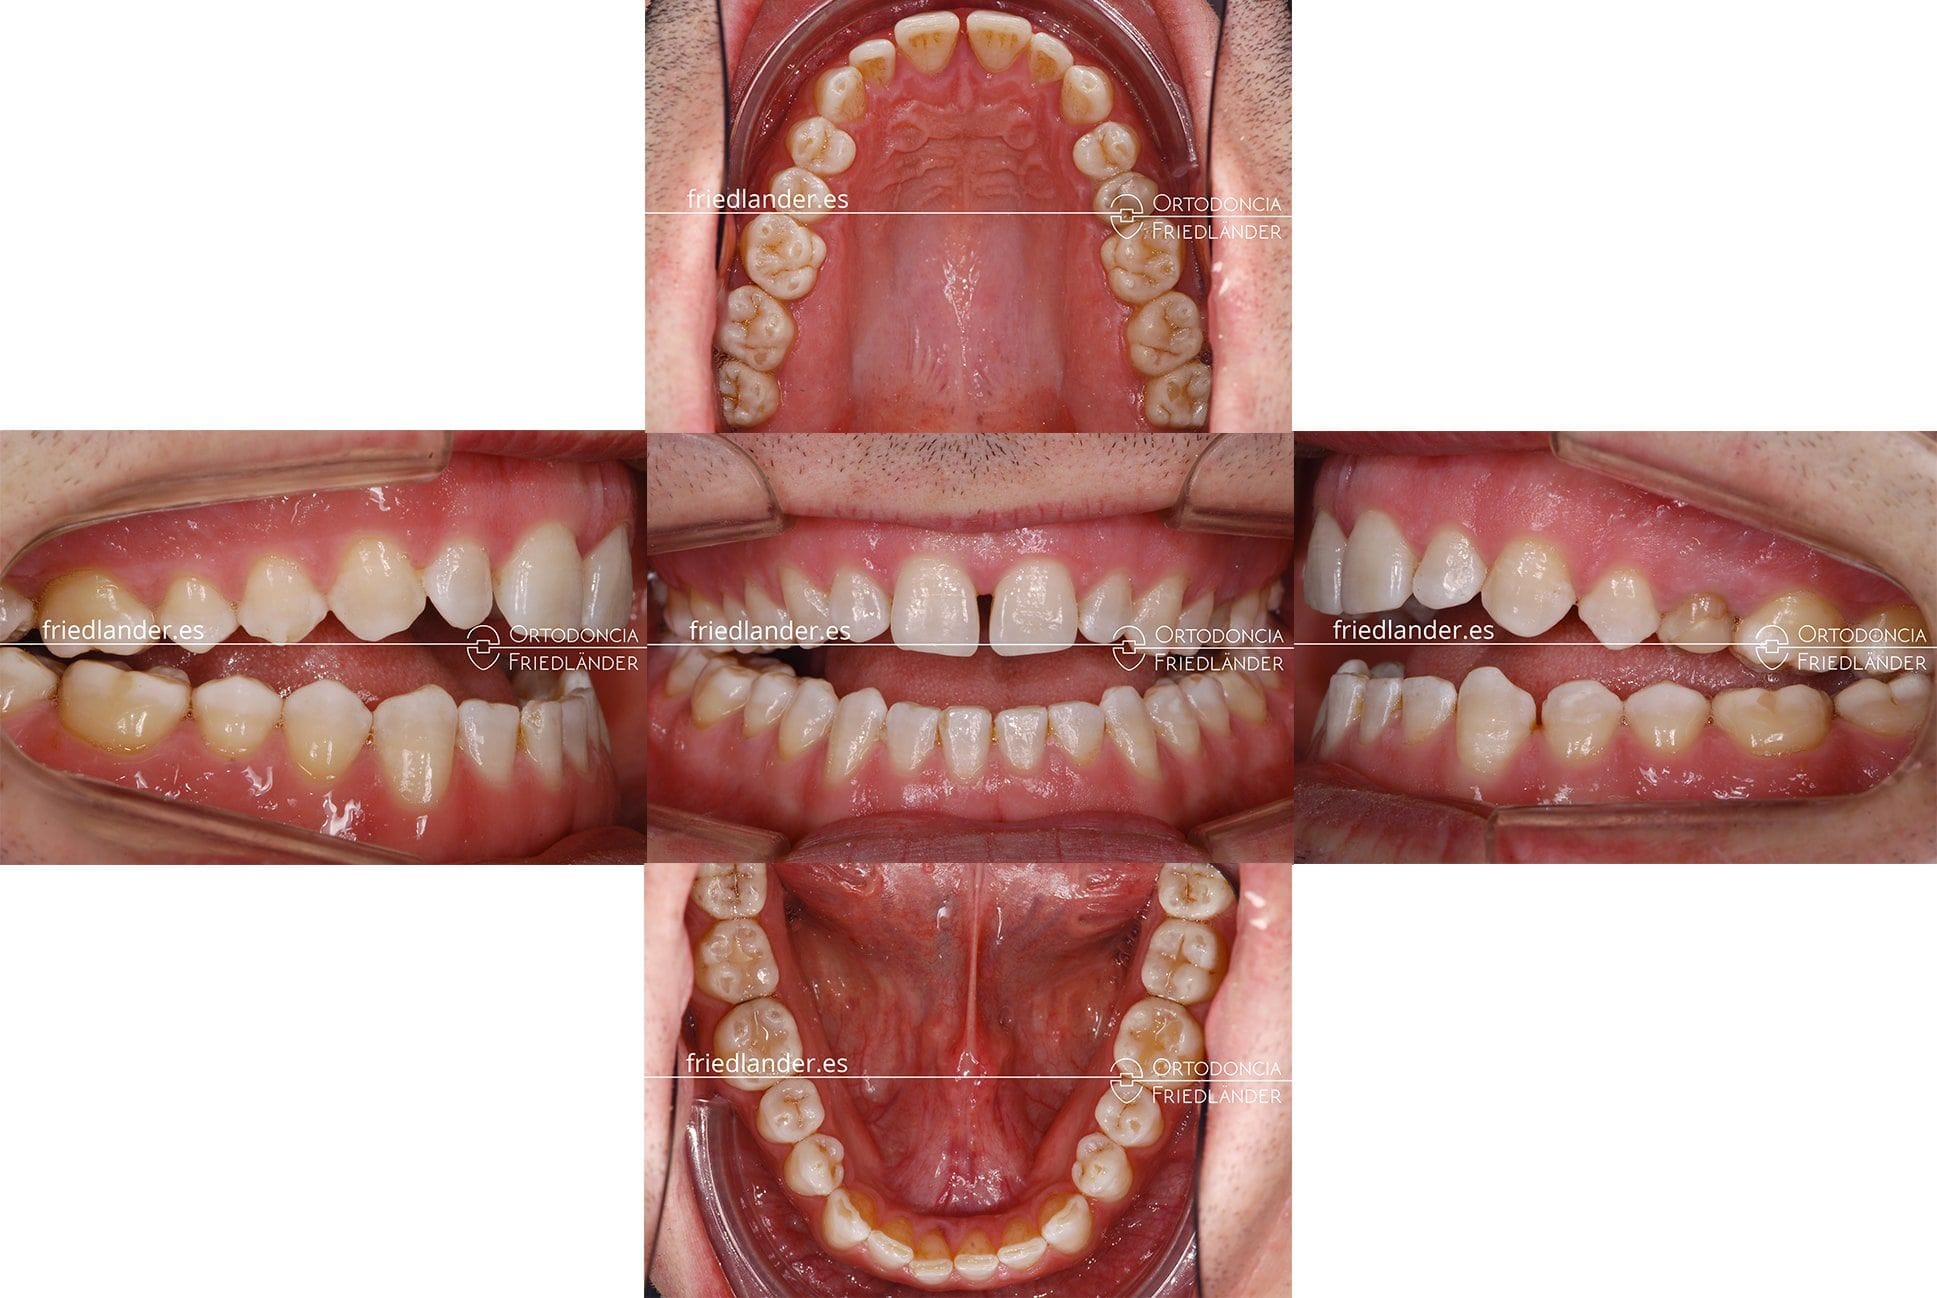

Este paciente de ortodoncia fue tratado en nuestra clínica en Barcelona durante 20 meses con brackets de autoligado y microtornillos. En la primera visita acude el paciente, de uno 35 años, buscando una solución para la maloclusión de mordida abierta anterior severa que presenta. Se ha visitado en varias clínicas de ortodoncia en busca de solución y en todas ellas le han ofrecido un tratamiento de ortodoncia con cirugía ortognática.

Al ver la boca del paciente hemos decidido hacer el estudio de ortodoncia y decidir si podemos solucionarlos con o sin cirugía.

Al hacer el estudio de ortodoncia decidimos simular el tratamiento que planificamos y por esta razón retiramos los molares de los modelos superiores, que son los que tocan antes de los demás. Al subir, o eliminar en los modelos, los molares superiores la mordida se cierra. Midiendo la cantidad de intrusión posterior de los molares superiores vimos que con tan solo 3mm de intrusión posterior podemos cerrar la mordida. En nuestras manos hacer 3mm de intrusión posterior es muy factible si usamos microtornillos. (en los casos 47, 46, 42 y 39 se puede ver más casos de mordida abierta tratados con microtornillos)

El paciente aceptó nuestro plan de tratamiento y empezamos el tratamiento con brackets de autoligado y microtornillos solo en la arcada superior.